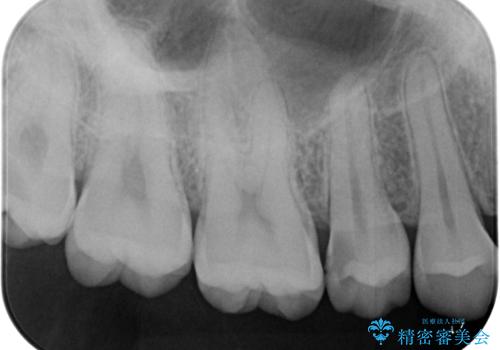

食べ物が頻繁に詰まるとのことで、レントゲンで確認したところ、歯間部に齲蝕が認められました。

ぱっと見ではわかりずらい齲蝕ですが、レントゲン写真でははっきりと確認することができます。

齲蝕がより進行すると神経の処置が必要になってしまう可能性があるため、早期発見・治療のための定期健診の重要性がわかります。